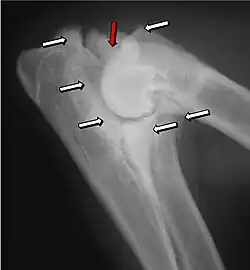

Ununited anconeal process

UAP is caused by a separation from the ulna of the ossification center of the anconeal process.[7] FMCP is caused by a failure of the coronoid process to unite with the ulna.